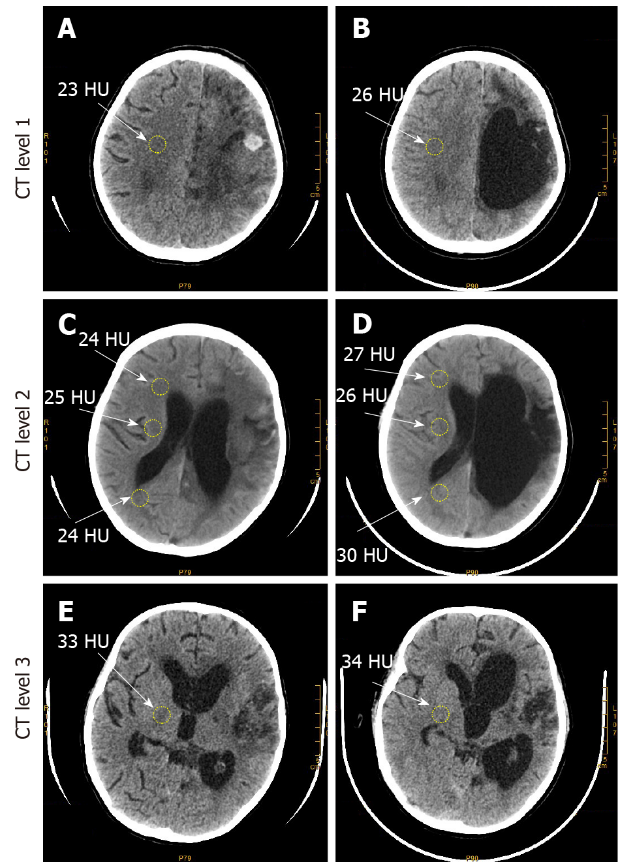

治疗前后CT结果

A、C、E:手术前在左半球观察到严重和大规模出血,包括覆盖左侧前额叶和顶叶区域以及大部分枕回的CT图像密度降低。和右侧相比,左侧脑室明显增大,并且由于血肿和脑水肿,中线脑结构也偏离了正常位置;

B、D、F:手术后,左半球因出血明显受损,左侧脑室明显增大,大脑严重萎缩。然而,在右半球观察到明显的脑软化,这通过与治疗前相似的脑群(黄圈)的CT数相比,多个脑区(黄圈)的CT数增加。

高浓度氢氧混合吸入后,左半球神经病理学稳定,右半球神经病理学减轻。